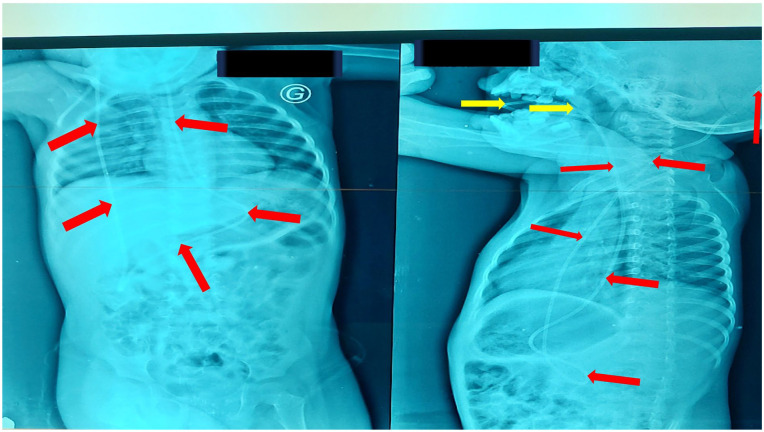

Ventriculoperitoneal shunting (VPS) is the surgical technique of choice to manage pediatric hydrocephalus. Despite having good results, it is prone to complications, some of which are rare. This is the case report of a 2-year-old male, with an uncomplicated VPS done at 6 months of age, presenting with vomiting, irritability, anorexia, and drooling. There was an oral protrusion of a tube dripping clear fluid. Imaging studies demonstrated evidence of gastric perforation with a cephalic migration and transoral protrusion of the distal end of the shunt tubing. A gastroplasty, and immediate revision of the distal shunt were done free of any complications. This case report underlines the importance of recognizing and managing trans-oral protrusion of the distal end of VPS system in a timely manner, and raises awareness of this uncommon complication and its potential influence on patient health and survival, given ventriculitis' high lethality.